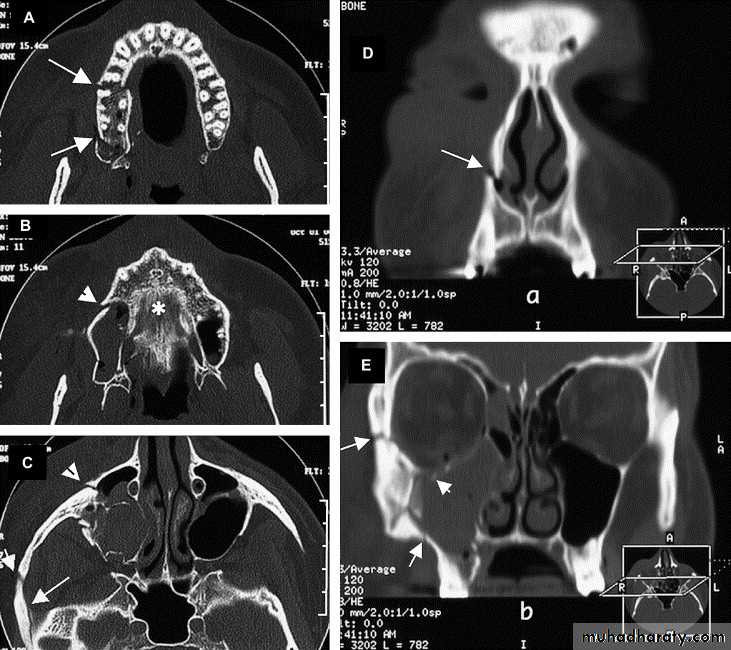

• B-maxillofacial computer tomography (CT/SCAN): which is the study of choice for evaluation of most of facial injuries include axial and coronal planes.

Maxillofacial CT